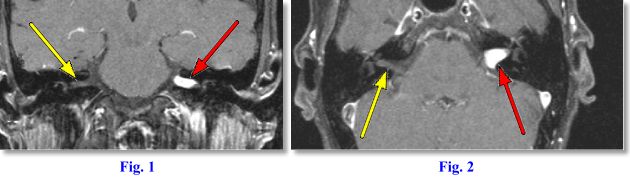

MRI Findings: Figs. 1 and Fig. 2 are thin (2 mm) post-contrast T1 weighted Fat Saturated (fat turns dark) images through the IAC’s performed on AIC’s ultrafast, high-resolution, high-field Siemens Symphony magnet. Fig. 1 is a coronal and Fig. 2 an axial image. They demonstrate a bright enhancing mass in the left cerebellopontine angle (CPA) extending into the left IAC (red arrows). A normal right IAC can be seen (white arrows).

Final Diagnosis: The MR findings are typical of an intracanalicular acoustic neuroma (AN). AN is also called vestibular schwannoma. A meningioma would also be in the differential diagnosis but much less likely, as they tend not to extend into the IAC. Other masses that can occur in the CPA (none of which with this appearance) include arachnoid cyst, metastasis, chordoma, aneurysm, other cranial nerve schawanomas, glomus jugulare, etc. ANs account for 5-7% of all intracranial tumors; 85% of all intracranial neuromas; 80% of all CPA tumors. Most AN’s are purely intracanalicular (95%) with remaining 5% arising at CPA with intracanalicular extension.